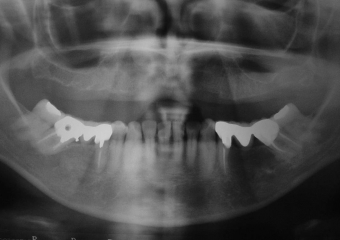

Raio X inicial